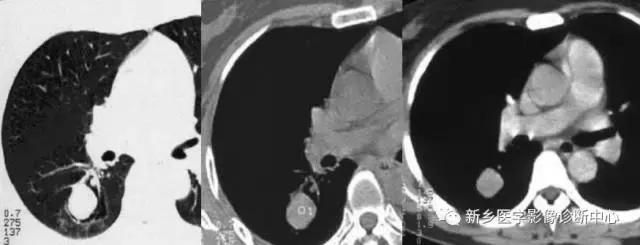

肺内血肿

有外伤史,胸痛,痰中带血或咯血。早期多为大片实变影,边缘模糊,2周后可出现类圆形密度均匀,边界清楚的球形肿块影。

下图为:车祸2小时血肿,治疗1周血肿,及治疗2周后血肿